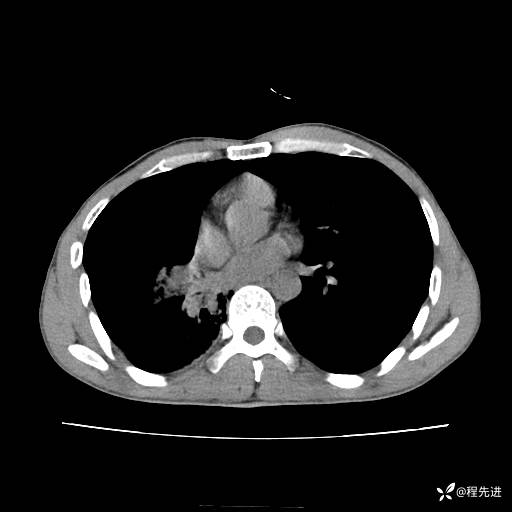

患者性别:男

患者年龄:49岁

主诉:咳嗽、胸痛1周

简要病史:1周前受凉感冒后开始出现咳嗽症状,阵发性连声咳,痰多,黄白痰,不易咳出,伴胸痛、气紧、胸闷,右侧为主,活动用力、呼吸时胸痛明显,曾在当地诊所贴敷膏药仍疼痛

体格检查:T:36.3 ℃ P:80 次/分 R:20 次/分 BP:120/88 mmHg,指脉氧饱和度97%,意识清晰,呼吸平稳,右侧第二、三肋骨压痛,可见膏药贴敷,皮肤无异常,双肺呼吸音粗,未闻及干湿性啰音。心率80次/分,节律整齐,无杂音。腹平软,全腹无压痛无反跳痛

临床诊断:社区获得性肺炎

CT平扫: